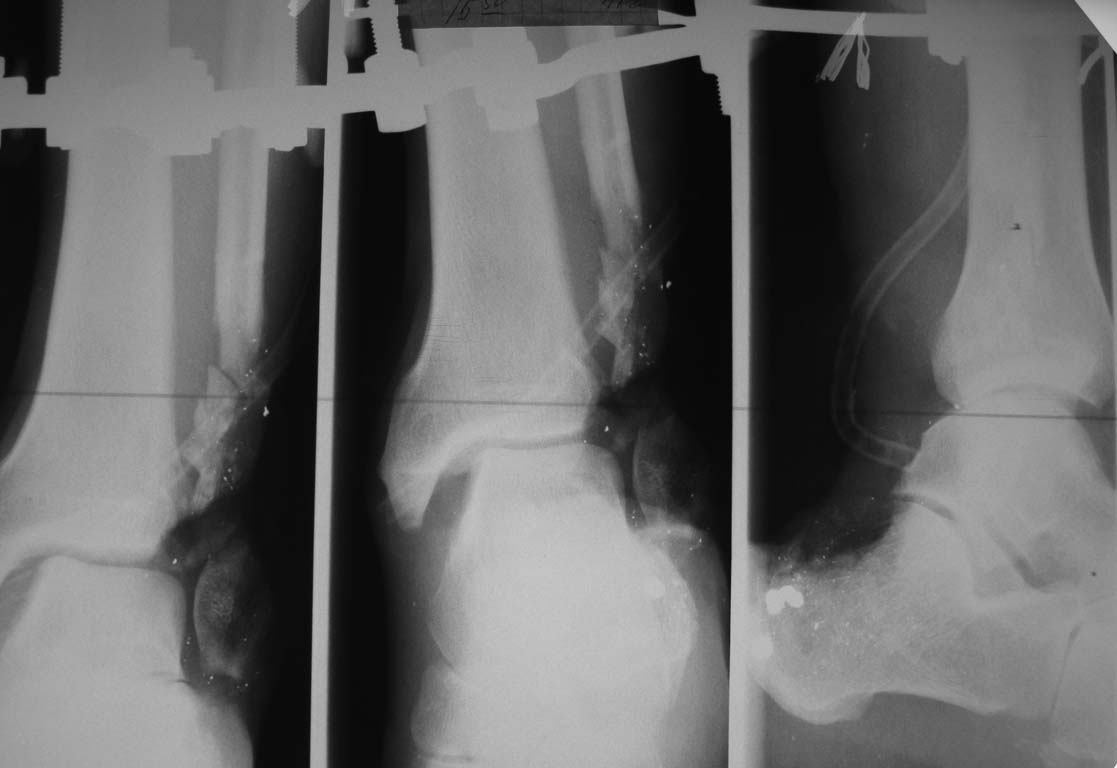

Уважаемые коллеги, представляется на обсуждение пациент с дробовым ранением нижней голени

в нижней трети.

Получил ранение при неосторожном обращении с оружием. Доставлен в ЦРБ, где выполнено

ушивание раны и иммобилизация гипсовыми лонгетами. При поступлении нами выполнена ПХО раны

с фиксацией в аппарате. Несколько дней проводилось лечение в повязке с низким давлением.

Рентгенограммы и внешний вид раны представлены во вложенном файле. Планируем: выполнить

артродез голеностопного сустава стержнем с АБ покрытием с замещением дефекта задней

поверхности несвободным лоскутом с противоположной конечности. Использовать

микрохирургическую технику возможности нет. Хотелось бы услышать мнение участников

форума. Спасибо!